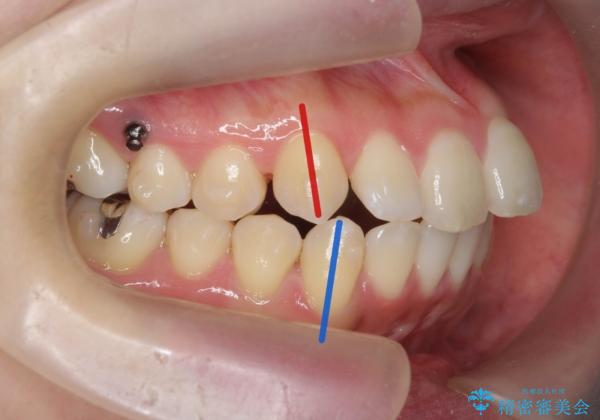

上下の歯は、上顎の歯が相対的に前に位置する咬合関係で押し出されるように前歯に角度がついている状態です。

咬合関係の改善、前歯の角度、がたつきを改善するため、マイクロインプラントを用いて上顎の奥歯を後方へ移動させていきます。